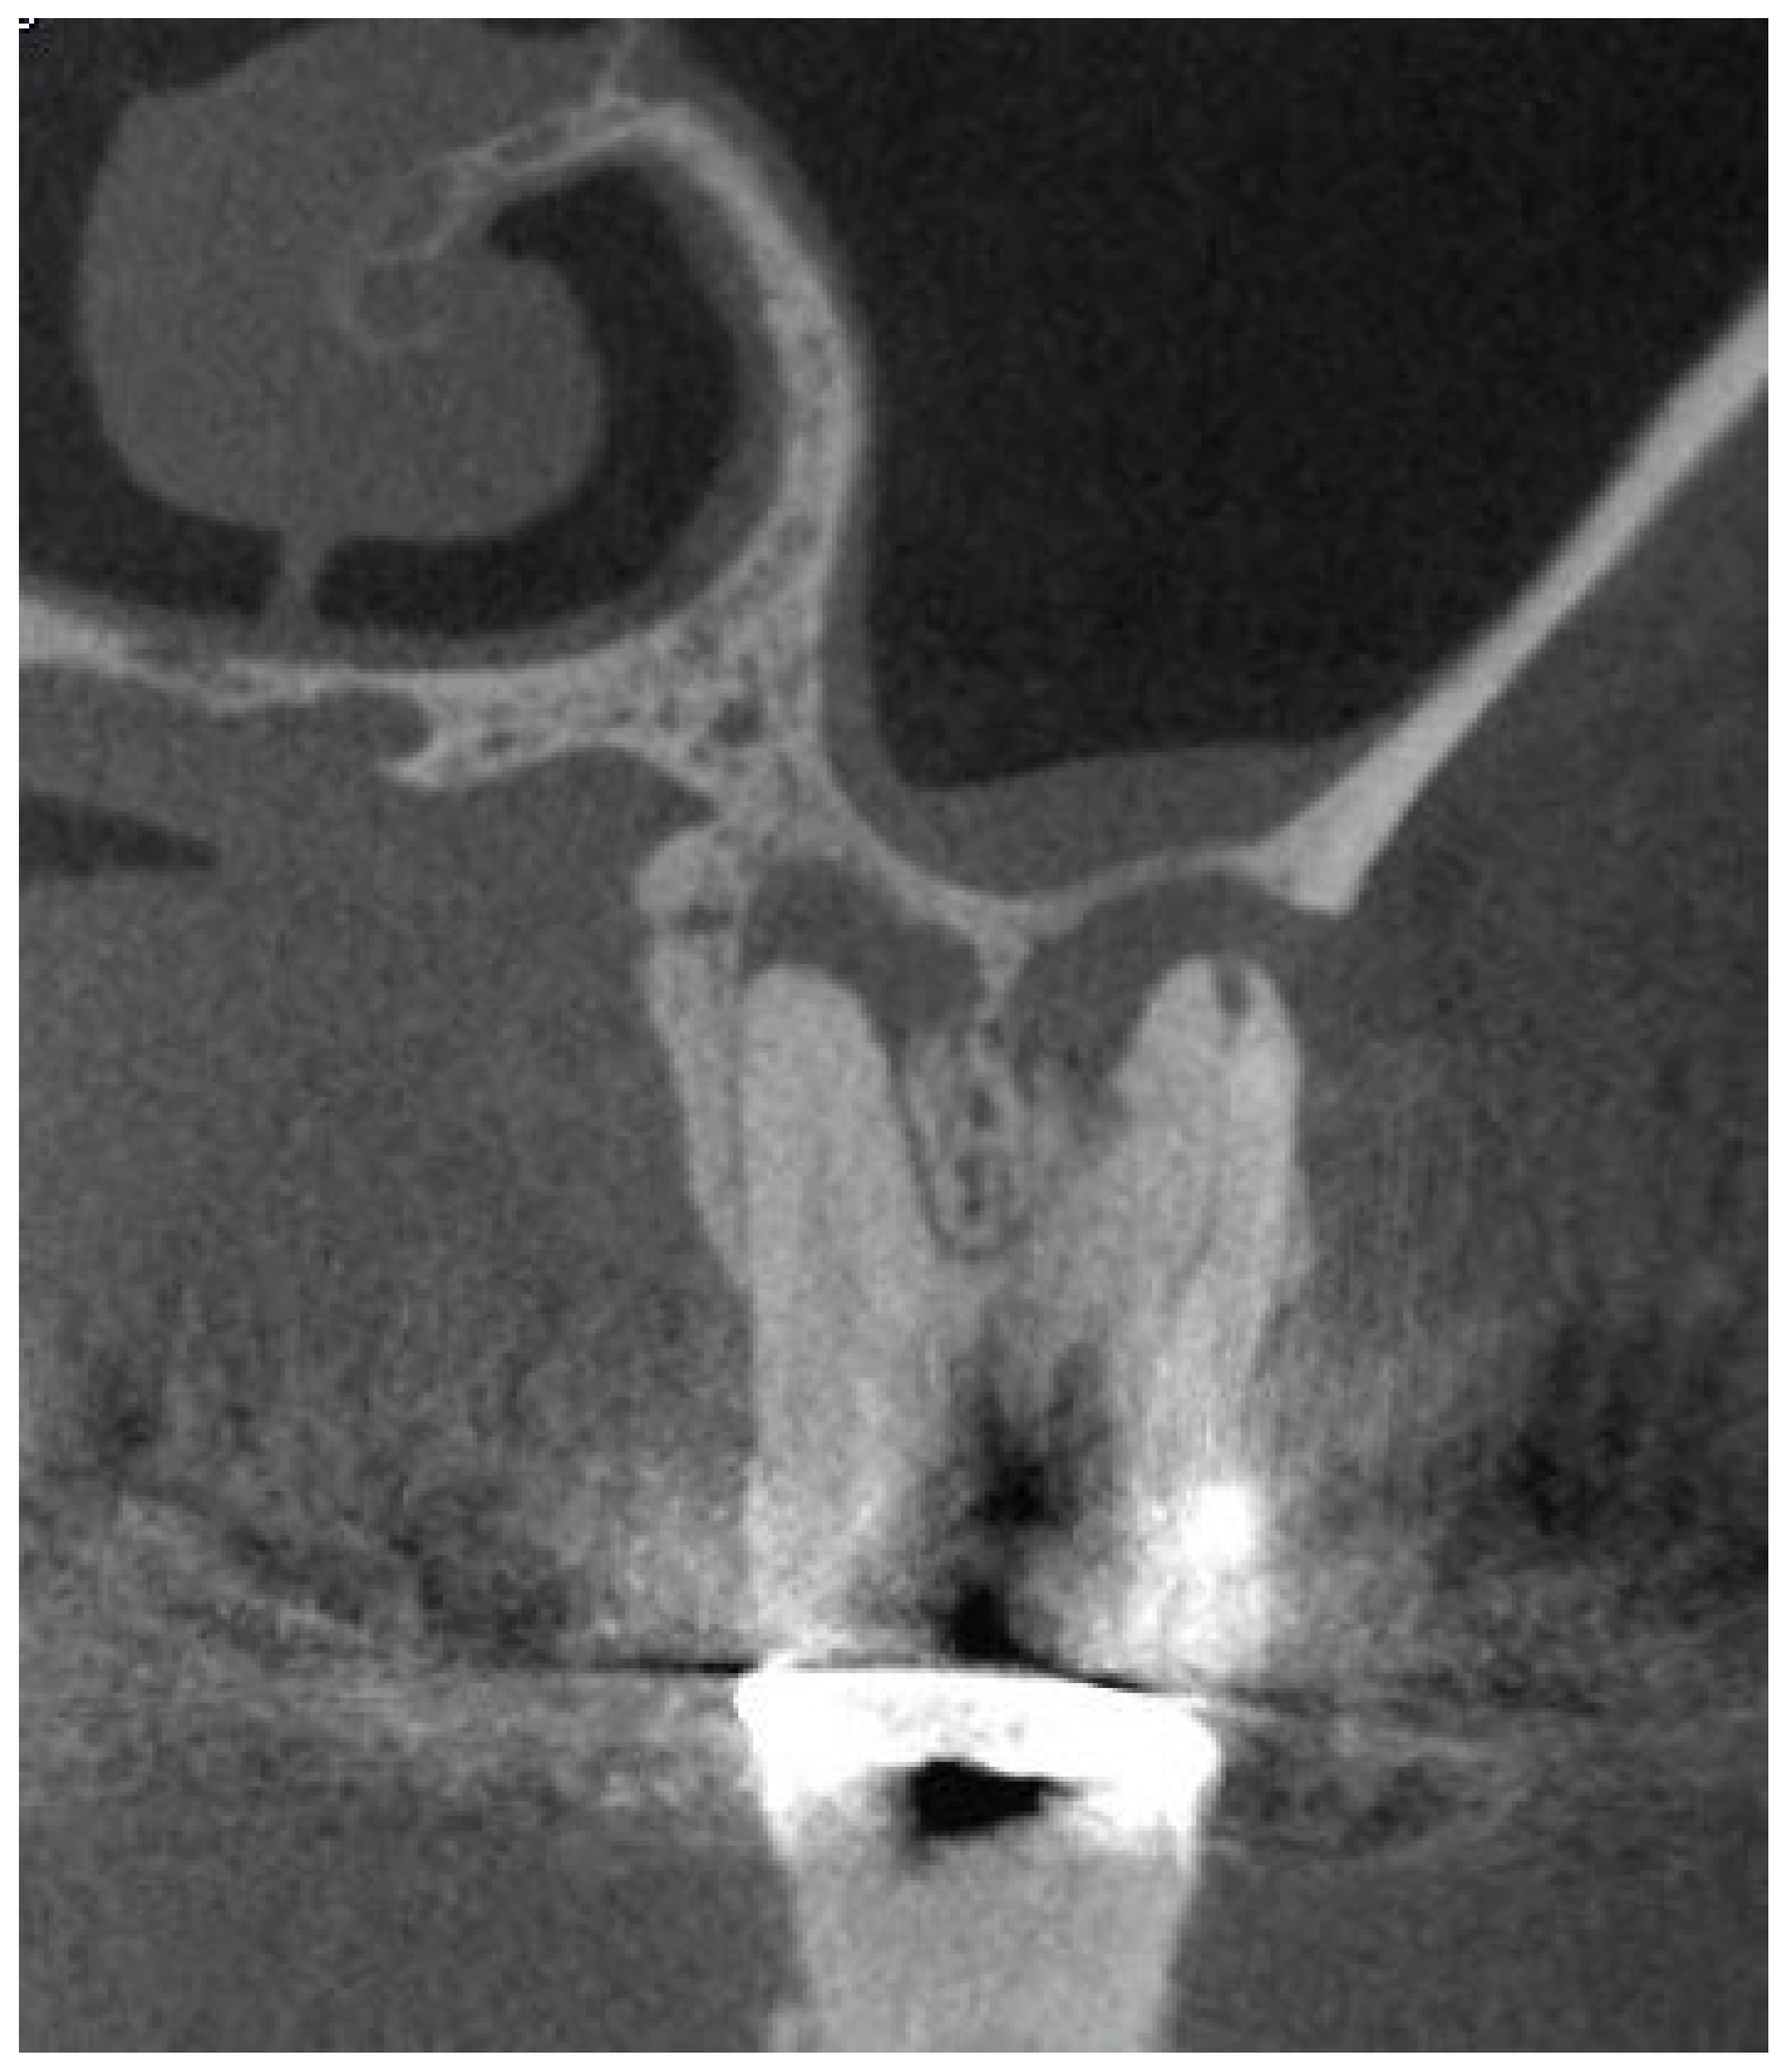

After the whole tomographic volume was analyzed in sagittal and coronal views, the sagittal slice that allowed the clearest visualization of the relationship between the apex and the maxillary sinus floor was selected and the linear distance between the 2 structures measured (Figure 1). The width of the sinus membrane was measured, whenever it was apparent, in the areas immediately adjacent to each tooth. The parameters set by Nurbakhsh et al. (2011) [44], that considered as normal, cases with up to 1mm thick membrane; mucositis when the membrane width was up to 3.54mm; and images suggestive of sinusitis in cases above 3.54mm were used as references to categorize the condition of each membrane studied (Figure 2). Besides that, the maxillary sinus condition was assessed using the LUND-MACKAY SCORE [45], in which, the maxillary sinus can be grouped in 3 categories according to the opacification detected on an image, being 0=completely clean sinus; 1=partial opacification; 2=complete opacification. The Lund-Mackay score was used because it is a simple score, that requires virtually no previous training and is frequently used by Otolaryngologists. [51].

Figure 1. Linear measures from the periapex to the cortical of the maxillary sinus floor.